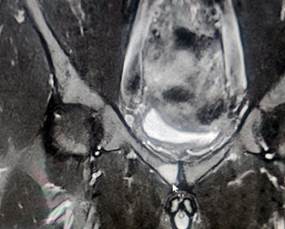

МРТ костей таза 19.07.2024г.: картина двухстороннего сакроилеита 1-2 ст., лонного симфизита, апофизита L2, L4, S1 позвонков и мелкоочагово-суставных фасеток истинных суставов позвоночника (с учетом данных МСКТ от 02.07.2024г., нельзя исключить проявления системного аутоиммунного воспалительного процесса) (рис. 2).

Рис.2. Магнитно-резонансная томография костей таза: лонный симфизит (оригинальные данные МРТ, выполненной в одной из частных клиник города)